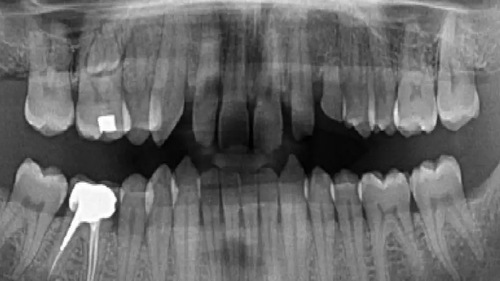

• <p><strong>FORMAT - JOURNÉE FOCUS</strong><br>📢 Cette formation est agréée par l'<strong>ANDPC.</strong>Réf. Action : 25232425003Session n° : 26.004<br></p> <p><strong>LES OBJECTIFS PÉDAGOGIQUES :</strong><br>- Connaître les principes d’utilisation et d’acquisition de la tomographie numérisée à faisceau conique.<br>- Appréhender la séméiologie radiologique tridimensionnelle au niveau cranio-facial.<br>-Apprendre les indications du CBCT dans les différentes pathologies dentaires et des structures maxillo-mandibulaires.<strong><br><br>IMAGERIE DENTAIRE</strong><br>Principaux examens d’imagerie en odontologie et chaîne de création de l'image.<strong><br><br>IMAGERIE 2D</strong><br>- La radiographie panoramique en 2023 : un outil indispensable ?<br>- Les capteurs numériques intra-buccaux : principes de fonctionnement et protocole d'utilisation des différents capteurs.<strong><br><br>IMAGE 3D</strong><br>- La tomographie volumique à faisceau conique ou Cone Beam Computed Tomgraphy (CBCT) :<br>- Principes physiques et techniques d’acquisition.<br>- Intérêts, limites et protocoles.<br>- Dosimétrie et choix de la taille d’acquisition pour les bonnes pratiques.<br>- Principes de justification et d’optimisation des examens 3D.<br>- Critères de lecture dans l’analyse des images.<br>- Rédaction d’un compte-rendu.Le CBCT en pratique clinique<strong><br><strong><br></strong>MISE EN PRATIQUE&nbsp;</strong><br>- Analyse CBCT sur ordinateur (un par praticien)<br>- Nombreux cas cliniques :implantologie, parodontologie,chirurgie buccale, endodontie,orthodontie, ...</p>